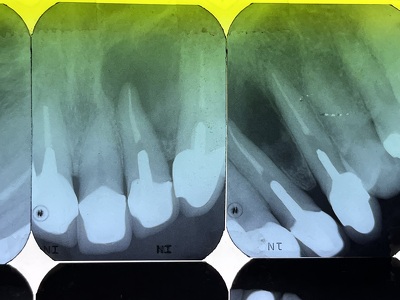

患者さんは静岡県からお出でになりました。レントゲン写真の右上2番の治療を依頼されました。

レントゲンでは上手く治療できているように見えますが治療結果は悪く、たびたび化膿を繰り返し、抜歯を進められていました。

当院で治療後のレントゲンです。根の尖にあった病巣が消失しています。